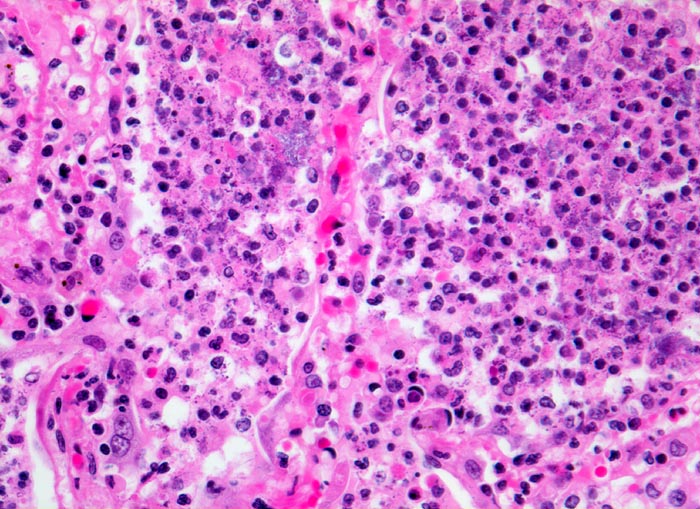

PathoPic ID 4652 - Bronchopneumonie: pneumonisches Infiltrat

Bronchopneumonie: pneumonisches Infiltrat

Entzündung infektiös

Lunge

Ausschnitt aus dem pneumonischen Infiltrat: die Alveolen sind gefüllt mit neutrophilen Granulozyten und feinkörnigen blauen

Bakterienhaufen.

320